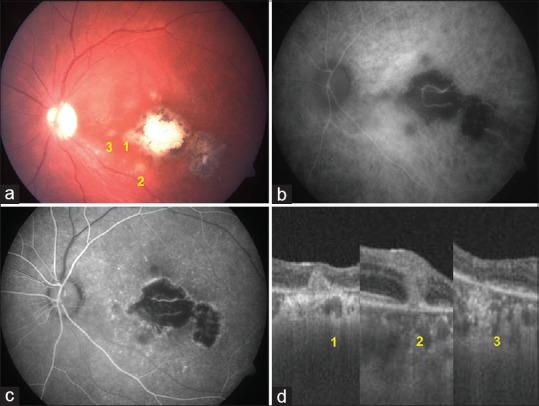

Results: We analyzed 34 eyes of 34 cases (22 males and 12 females). PORT lesions appeared as deep, dull, yellowish-gray outer retinal lesions, either as satellite lesions to a TRC (n = 30) or isolated macular punctate lesions (n = 4). The mean lesion size was 562 μm (50-1000). The recurrence rate was high (23.52%), manifesting as either typical TRC (n = 4) or new satellite PORT lesions (n = 4). Active lesions had hyperreflective outer retinal foci on optical coherence tomography (OCT), hyperautofluorescent in the active phase, and stippled upon resolution. Healed lesions exhibited outer nuclear layer thinning and outer retinal atrophy on OCT and were hypoautofluorescent.

Conclusion: PORT lesions were observed as multiple punctate lesions, either adjacent to TRC in active or healed phases or as isolated macular punctate toxoplasmosis. Autofluorescence, angiography, and OCT assist in differentiating active from healed lesions. The fate of PORT lesions was healing with granularity, fading, or complete resolution. Some cases recurred with new satellite PORT lesions, whereas others progressed to typical retinochoroiditis or CNVM.